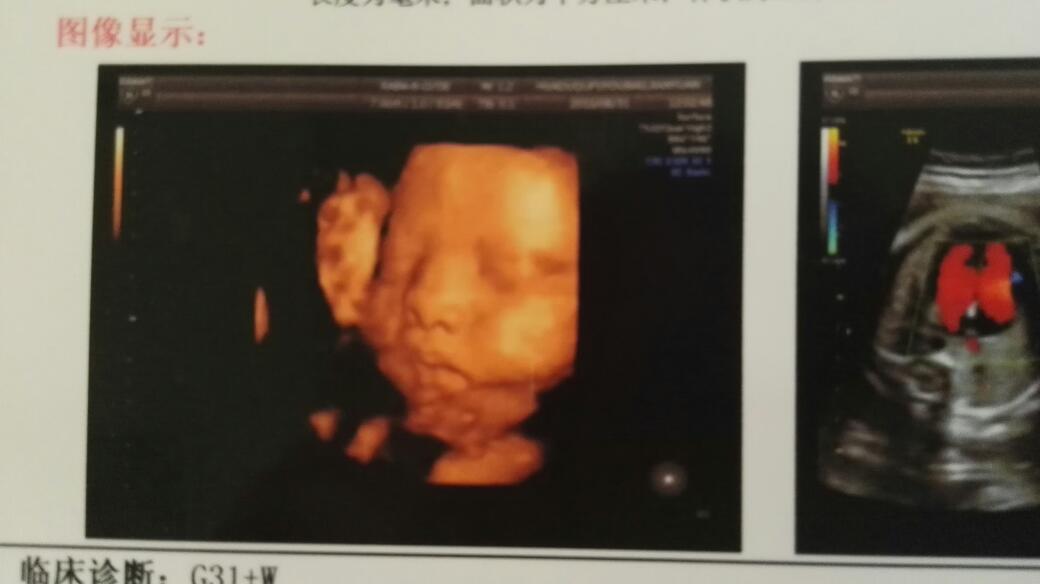

您好,彩超检查是在胎兵报儿的不同时期检查不同的发育情况,四维彩超可以更好的看出胎儿的祸吊实发育变化情况,排除胎儿畸形,但是也不是绝对的。根据您的图片是无虏竞法看出胎儿发育变化情况的,建议您定期进行产检,密切观察胎儿的发育变化情况。